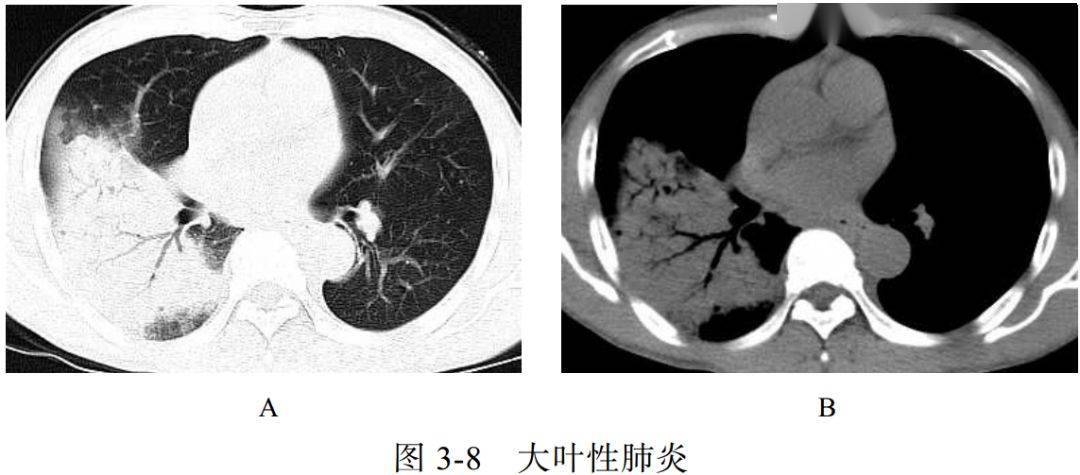

影像学表现:

(1)充血期肺组织呈边缘不清的云雾状影,实变期呈大片实变影(图 3-8A)、充气支气管征(图 3-8B),消散期呈散在斑片状影

(2)肺炎链球菌肺炎与肺炎克雷伯菌肺炎的区别:前者支气管充气征清晰可见,可达胸膜下;后者因分泌物黏稠,支气管充气征显示不佳